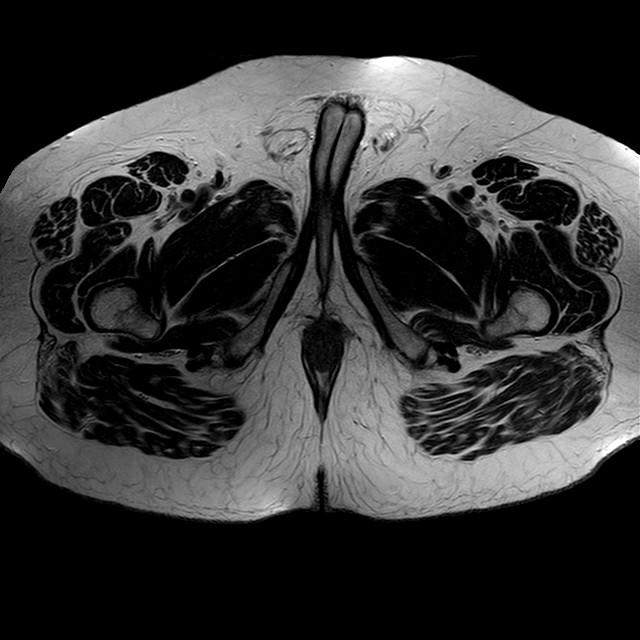

Esami: RMN BACINO

eT2w TSE

Evidenti e simmetriche alterazioni osteofitosiche in regione coxo femorale con riduzione delle rime articolari. Degenerazione completa del cercine glenoideo. Non attuali segni di versamento articolare. Non segni di edema osseo che escludono attuale algodistrofia od osteonecrosi. Lieve e simmetrica riduzione del trofismo della muscolatura glutea.